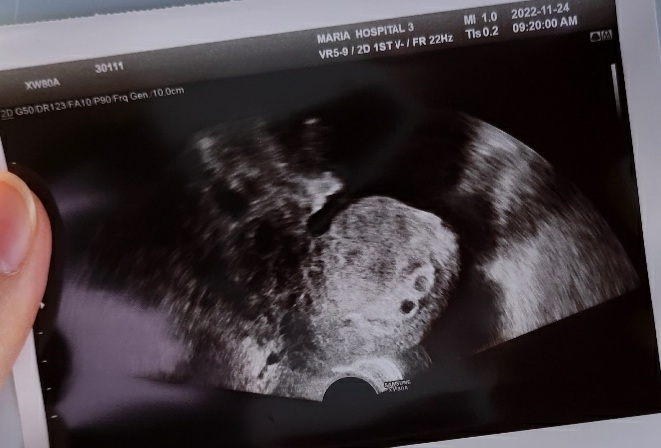

처음엔 인공수정으로 시도를 했었는데 세 차례 다 실패로 끝나서 최종적으로 시험관 시술을 받게 되었는데 첫번째 시험관 시술만에 바로 성공하여 드디어 기다려왔던 임신을 하게 되었다.

난임병원에서 인공수정이나 시험관 시술을 받으면 쌍둥이가 생길 확률이 높다는 말을 예전부터 들어왔었는데 아니나 다를까?

우리에게도 드디어 아기가 찾아왔다!

그것도 둘 씩이나! 쌍둥이로!

시험관 시술 때 35세 이하는 수정된 난자를 2개 넣고 35세 이상은 3개를 넣는다고 한다.

그래서 우리는 35세 이하라 2개를 넣었는데 2개가 다 착상에 성공한 것 같다.

임신 초기에는 이런저런 변수들이 많다고 하여 안정기라는 12주에 접어들 때까지 최대한 조심하며 지내고 있는중인데 어느덧 7주가 되었다.

그러다 임신 7주차에 아기 심장소리를 병원에서 듣고 오니 이제서야 드디어 실감이 나기 시작했다.

초음파 보니 아직은 아주 작은 우리 아가들의 심장이 콩닥콩닥 열심히 뛰는 모습이 보였다.

작은 우리 아가들 열심히 잘 자라주고 있구나 하는 생각에 우리 아가들이 기특하기까지 했다.